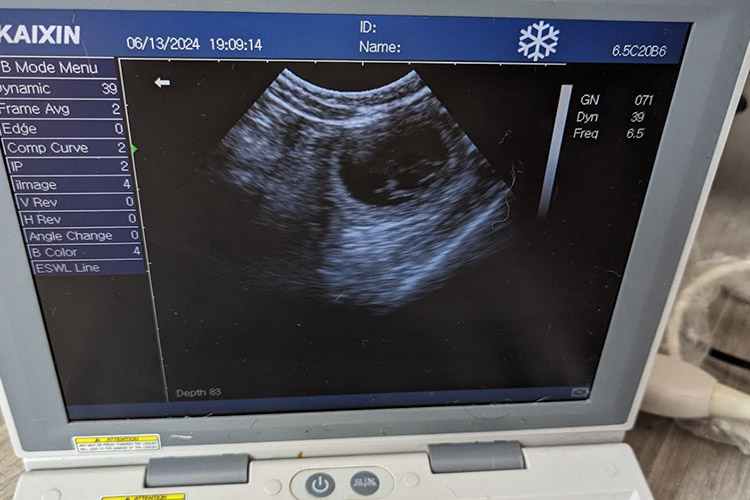

At Top to Tail Fertility & Grooming in Morecambe, we use a high-tech, high definition kx5600v veterinary ultrasound scanner to confirm and monitor pregnancies throughout the gestation. We provide pregnancy ultrasound scans to detect and confirm pregnancy and we can monitor your bitch and her litter progress throughout the gestation.

The ultrasound gives an indication of litter sizes. More importantly, we can estimate the whelping date, allowing you, to optimise your dog’s care and feeding routines and prepare for the whelp date. Get in touch with Morecambe Canine Fertility to book an appointment!

Unlike X-rays, radiation is not used for ultrasound examination. Ultrasound imaging works via sound waves and provides clear information useful for diagnosing and measuring a pregnancy.

The scans can be carried out standing or lying down, whichever is more comfortable for your dog and we use a use a water-based gel that is safe to use on the dog’s abdomen.